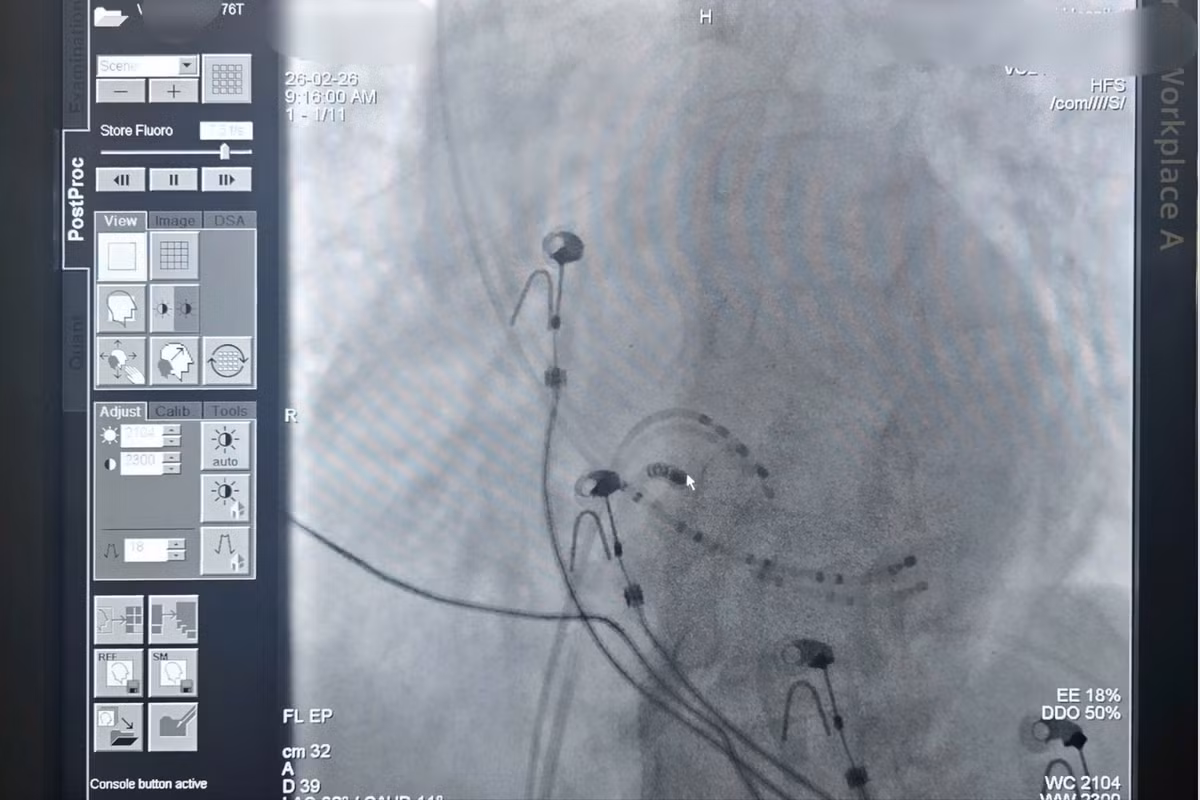

Vì vậy, các bác sĩ tim mạch can thiệp về nhịp quyết định làm thăm dò điện sinh lý buồng tim, xác định chính xác cơ chế gây cơn nhịp nhanh... sau đó đốt triệt thành công ổ rối loạn nhịp bằng sóng cao tần. Ca can thiệp diễn ra an toàn, không biến chứng. Nhịp tim bệnh nhân ổn định ngay sau can thiệp, huyết động cải thiện rõ rệt, nguy cơ tái phát được kiểm soát lâu dài.

Vị trí đích triệt đốt RF thành công cơn tim nhanh.